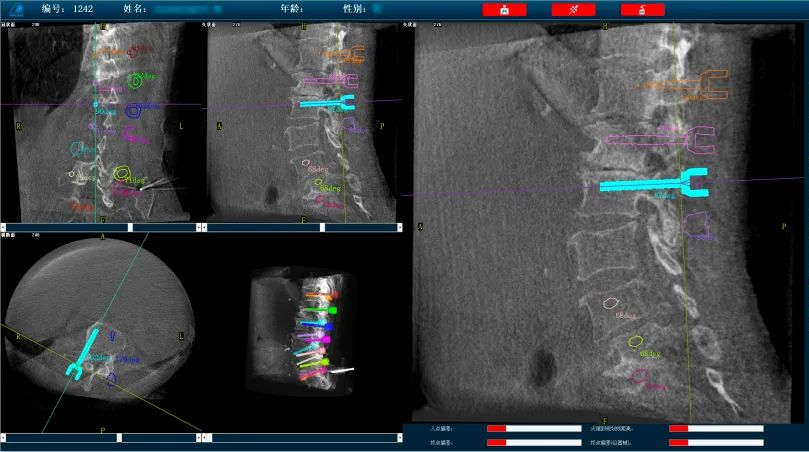

而外科手術機器人與三維C形臂配合,基于3D影像數(shù)據(jù),利用手術規(guī)劃軟件,術前模擬植入物狀態(tài),引導醫(yī)生進行預手術規(guī)劃,輔助評估和及時調整手術路徑規(guī)劃設計,機械臂準確運動到規(guī)劃位置,借助導向套筒,為醫(yī)生提供穩(wěn)定的導針置入路徑。外科手術機器人以實現(xiàn)準確、微創(chuàng)手術為首要目標,通過手術機器人準確定位可以減小患者手術過程中的開口大小,減少神經損傷風險,實現(xiàn)手術操作的準確度和安全性。

普愛醫(yī)療骨科手術機器人可廣泛地應用于多節(jié)段脊柱外科手術,輔助醫(yī)生定位病灶部位,為脊柱外科手術(經皮椎體成形術、椎弓根螺釘內固定術等術式))提供術前手術流程規(guī)劃、入釘位置、角度可視化引導,模擬仿真入釘輔助。產品優(yōu)勢特點如下:

外科手術機器人配備高精度光學追蹤系統(tǒng)和機械臂,可基于3D影像數(shù)據(jù),利用手術規(guī)劃軟件,引導醫(yī)生進行預手術規(guī)劃,輔助準確定位植入物或手術器械,精度可達亞毫米級。尤其對高風險、復雜程度高的手術具有明顯優(yōu)勢,可有效降低手術風險。

操作流程簡單化:多次手動入釘定位,操作繁瑣,骨科手術機器人可以實現(xiàn)多枚螺釘路徑一次性規(guī)劃,節(jié)省規(guī)劃定位時間,簡化手術操作流程,提高置釘效率。

復雜手術標準化:直觀的軟件操作界面引導,減少手術中的不確定環(huán)節(jié),使得復雜手術流程標準化,讓從業(yè)經驗不足的醫(yī)生也能快速掌握,縮短醫(yī)生的學習曲線。